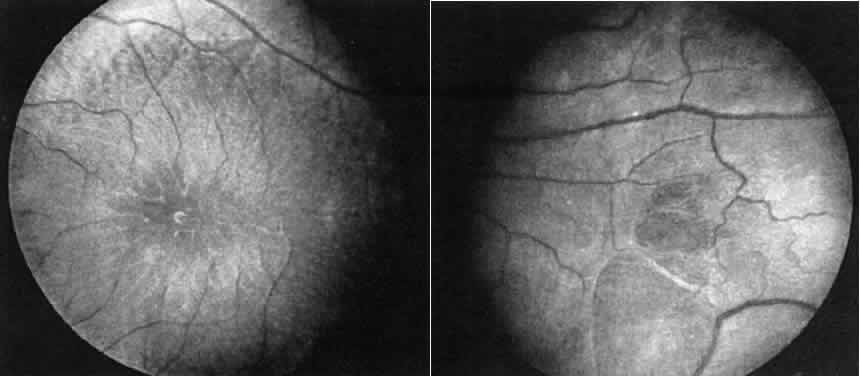

in the absence of any subjective complaints.12 These may consist of an unusual scintillating reflex in the macular area

or a clumping of pigment in the periphery (Fig. 13). However, these changes are not always seen. In such cases electrophysiologic

studies provide the answer, for it has been found that certain

electrophysiologic abnormalities also are seen in the majority of female

carriers, even those with no fundus abnormalities. These consist

of a prolonged photopic b-wave implicit time and/or a reduction in the

amplitude of the scotopic b-wave in a fully dark-adapted eye.13  Fig. 13. Female carrier of X-linked retinitis pigmentosa. Fundus photographs of

a 48-year-old female with vision of 20/20 OD and OS. Left. Macular area shows an unusual scintillating reflex around the entire parafoveal

region. Right. Retinal periphery showing an isolated area of retinal pigment epithelial

loss with associated clumps of pigment. Fig. 13. Female carrier of X-linked retinitis pigmentosa. Fundus photographs of

a 48-year-old female with vision of 20/20 OD and OS. Left. Macular area shows an unusual scintillating reflex around the entire parafoveal

region. Right. Retinal periphery showing an isolated area of retinal pigment epithelial

loss with associated clumps of pigment.